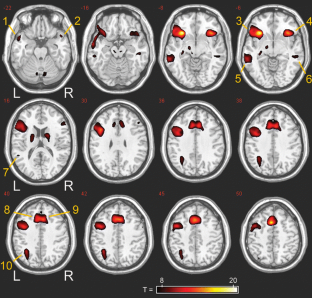

Results

Extensive frontal, temporal and parietal activations were found. Seventy-eight percent of the subjects showed left-hemispheric dominance, 5% showed right-hemispheric dominance, and 17% had bilateral language representations. The incidence of right-hemispheric language dominance was 4.3 times higher in a left-hander with a handedness quotient (HQ) of −90 than in a right-hander with a HQ of +90. The RC was 0.61 for combined ROIs (global network). Strong correlations were found between the two session LIs (r = 0.95 for the global network).